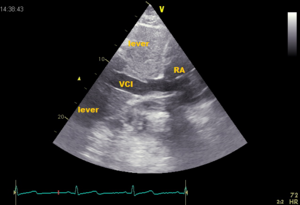

Echocardiographic view

SubcostaalVCI.png VCImmode01.jpg

Subcostale view M-mode collapse VCI